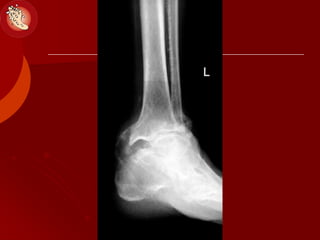

The Charcot Joint

 Deformily 

 Instability 

 Pain 

 Prophylactic Surgery?

 Anthrodesis (Regidity)

Diabetic Charcot Arthropathy

RELOCATION ARTHRODESIS

The Charcot Joint Deformily   Instability   Pain   Prophylactic Surgery?  Anthrodesis (Regidity) MIS